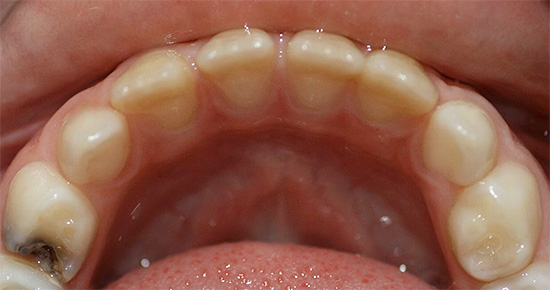

Nella foto: la carie in una fase iniziale di sviluppo:

Questo stadio di sviluppo della patologia è chiamato stadio del punto bianco: qui si verifica solo il danno iniziale allo smalto e la formazione di pori in esso sotto l'influenza di acidi aggressivi dalla cavità orale. Lo smalto perde la sua lucentezza, acquisisce un colore bianco più chiaro e saturo.

Ecco alcune altre foto di carie sul palco spot: